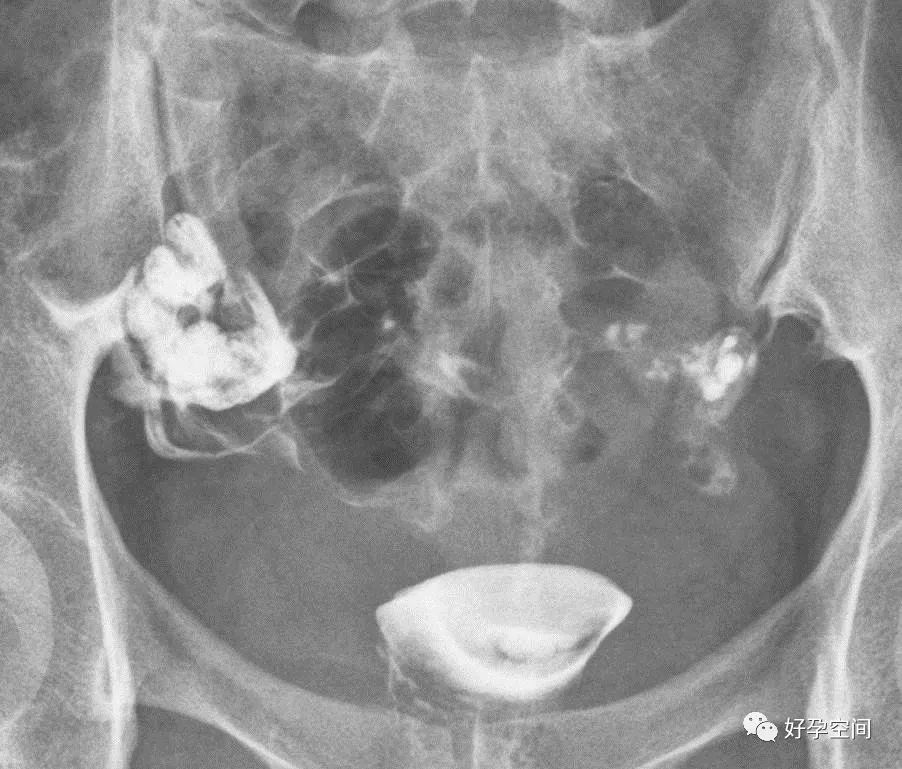

3、骨斑点症

骨盆诸骨均可见多发小圆形高密度影

5、盆腔陈旧性结核钙化灶

盆腔内见多个片状及点状高密度钙化影